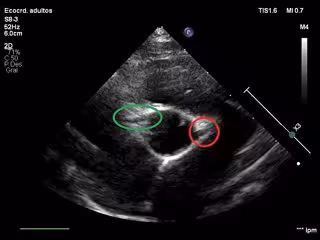

Imagen de un ecocardiograma en el que aparecen ambas arterias coronarias. Redondeada de color rojo la arteria coronaria izquierda y de color verde la arteria coronaria derecha

Imagen de un ecocardiograma en el que aparecen ambas arterias coronarias. Redondeada de color rojo la arteria coronaria izquierda y de color verde la arteria coronaria derecha - UPM